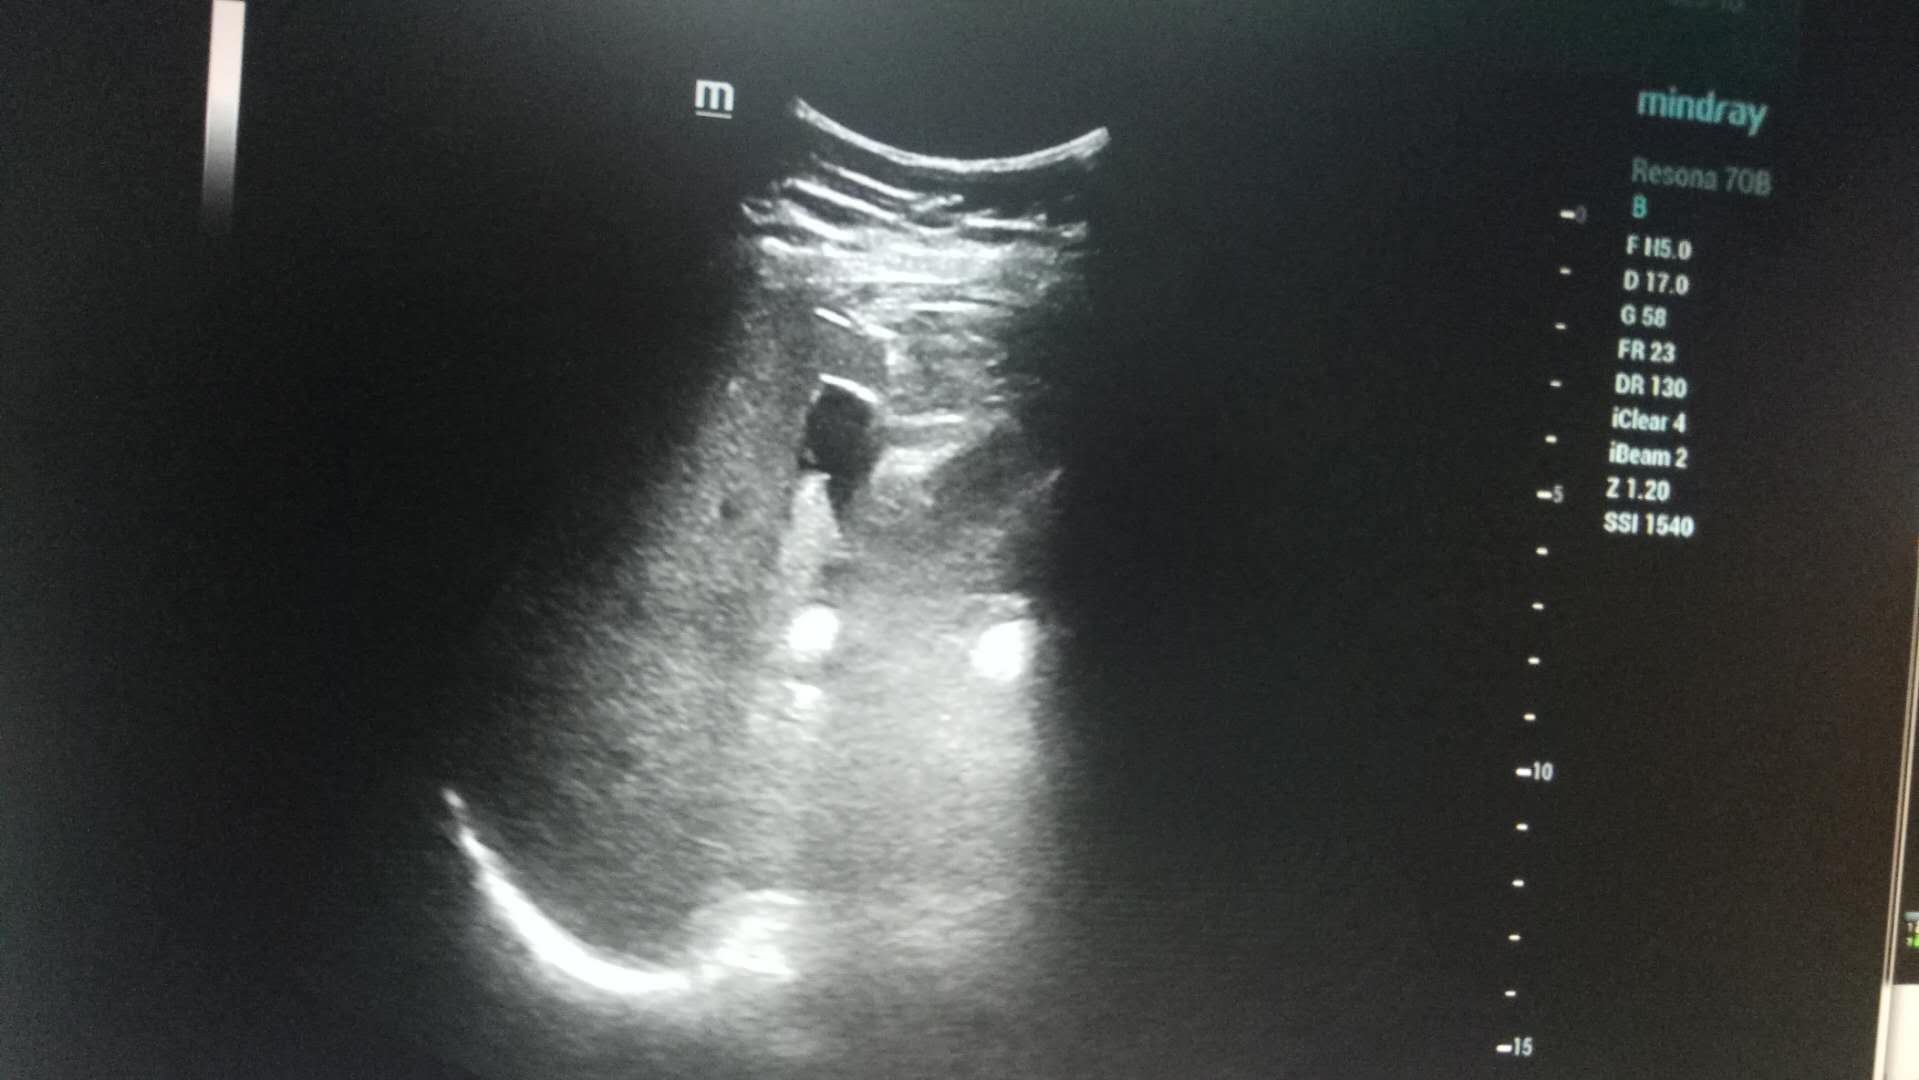

近日,21点游戏攻略站 超声科在高陵区医院成功开展了一例超声引导下肝囊肿抽吸硬化治疗术。患者前段时间查出肝囊肿,因开腹手术风险性大且痛苦,遂联系了高陵区医院超声科,在21点游戏攻略站 超声科主任展小军与对口支援医生杨艳秋的紧密配合下,短短30分钟,通过一根穿刺针,直径近7cm的肝囊肿就被完全抽吸硬化完毕,患者生命体征平稳,休息几小时后已活动自如。

超声介入微创诊疗技术是在实时超声的监视和引导下,完成各种穿刺、活检以及抽吸、插管、注药治疗等操作,达到与外科手术相当的效果,具有创伤小、恢复快、无辐射、介入治疗定位精确等优点。可治疗全身各部位囊肿,尤其是巧克力囊肿效果更佳,还有全身各部位肿瘤的活检和治疗,超声引导下微创治疗是未来医学发展方向。